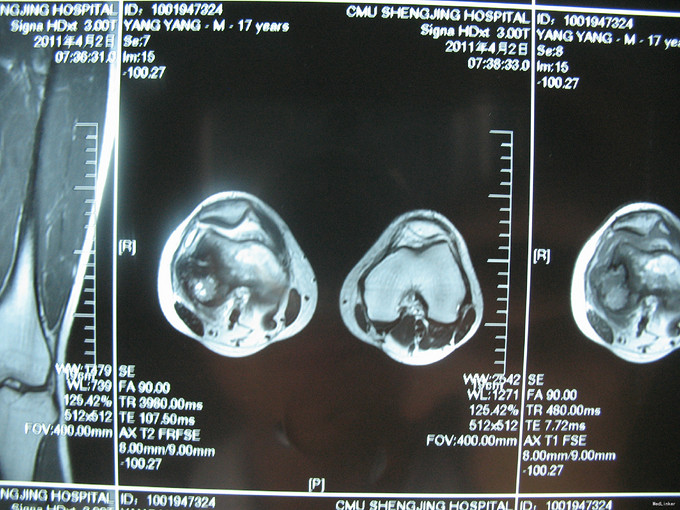

右膝上疼痛2个月肿胀一周 患者2个月前无明显诱因出现右膝上疼痛,逐渐加重,一周前活动后加重明显并开始出现肿胀,右膝关节活动受限,于当地医院行CT及MRI检查考虑为恶性肿瘤,遂来我院治疗。

右膝上股外侧肿胀明显,压痛(++),皮温略高,皮色正常,右膝关节屈伸活动明显受限。

入院后完善相关检查,诊断为股骨恶性肿瘤,考虑为骨肉瘤。切取部分肿物病理活检。病理明确诊断股骨骨肉瘤后,给予新辅助化疗。化疗效果明显,手术行瘤段切除人工假体置换术。